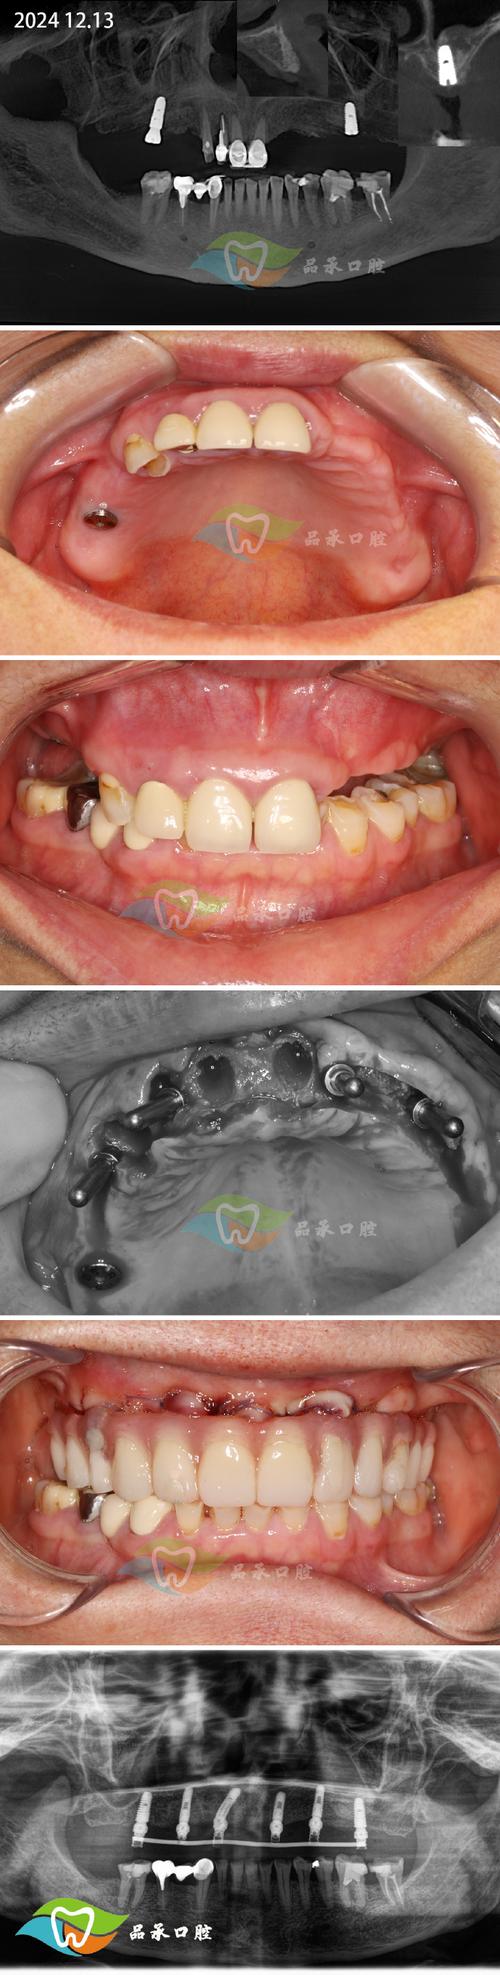

正常情况下,牙齿缺失后,牙槽骨会因失去功能性刺激而逐渐吸收萎缩,尤其是缺牙时间超过3个月的患者,牙槽骨宽度可能减少40%-60%,高度降低25%-30%,直接导致种植体植入空间不足或稳定性欠佳,骨移植植牙的核心临床意义在于:通过增加骨量,扩大种植适应证,避免因骨量不足导致的种植失败或复杂手术(如上颌窦提升、下牙槽神经移位等),提高种植体的长期成功率。

骨移植植牙手术需严格遵循“精准评估、无菌操作、生物相容”原则,通常分为术前准备、植骨手术、种植体植入及最终修复四个阶段,其中植骨手术是核心环节,具体流程如下:

通过CBCT(锥形束CT)三维重建测量牙槽骨的厚度、高度、密度及重要解剖结构(如下牙槽神经管、上颌窦底)的位置,结合口内检查和全身病史(如糖尿病、骨质疏松、吸烟史等),制定个性化手术方案,对于骨量严重不足者,可能需结合模型外科或3D打印导板辅助定位。

种植体植入与修复

植骨术后需等待4-6个月(自体骨可缩短至3-4个月),待移植骨与宿主骨完全整合(CBCT显示骨密度接近宿主骨),再行二期手术暴露种植区,植入种植体,术后3-6个月,待种植体与骨组织形成骨结合(osseointegration),最终完成牙冠修复,实现功能恢复。